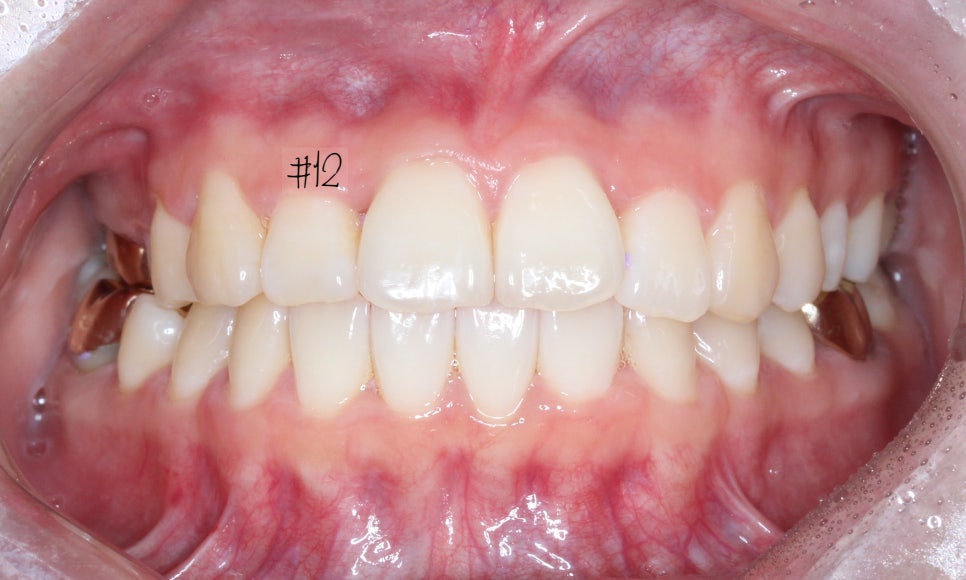

꽤 많이 개선이 되었지만

아직 #12가 배열이 잘 되었다기 보단

그냥 거꾸로 물리던 것이 해소 된 정도입니다.

약간 뻐드러진 느낌과

치축만 조금 더 개선 시키고 마무리 하기로 했습니다.

마무리 한 모습입니다.

브라켓을 붙이고 진행한 것은 아니라

디테일하게 중심선을 맞추거나

구치부 교합까지 완벽히 잡진 못하지만

환자분께서 원하시던

#12가 들어가 있던 모습과

뻗쳐보이는 느낌을 개선 후 마무리를 했습니다.